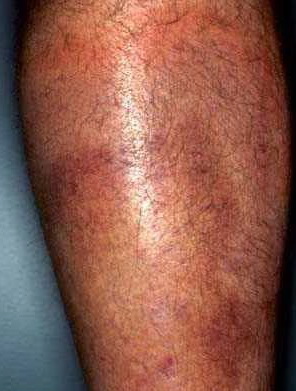

Lesions of urticarial vasculitis initially appear as erythematous wheals (see image below). As the lesions progress, purpura may develop. Often, the urticarial vasculitis lesions resolve with postinflammatory pigmentation. Annular or targetoid lesions may be observed.